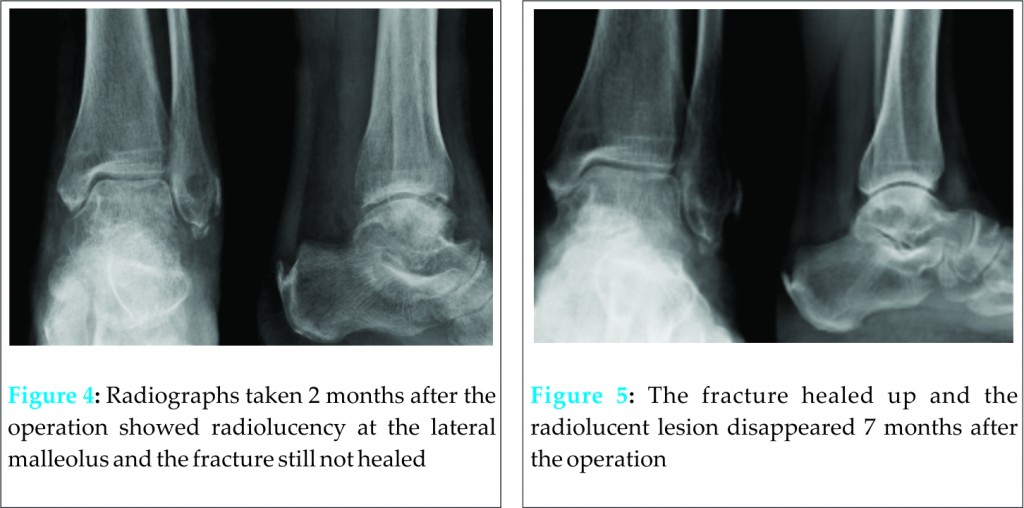

Computed tomogram confirmed cortical rim avulsion fracture and the diagnosis of Eckert and Davis grade 3 superior peroneal retinaculum injury (Fig 2). Endoscopic superior peroneal retinaculum reconstruction was performed (Fig 3).

Computed tomogram with transverse view of the lateral malleolus can be used for preoperative planning of arthroscopic lateral ligamentous reconstruction of superior peroneal retinaculum reconstruction. This allows the surgeon to select the anchor of appropriate size and length and the correct site and direction of insertion [8,11]. In general, anchor of spike mechanism would be more suitable than that of screw-in mechanism as the length of the anchor is shorter. Moreover, the direction of insertion is best along the diagonal of the lateral malleolus as it is longer than the transverse or anteroposterior dimensions.